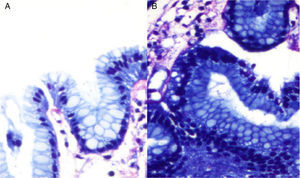

Upper gastrointestinal endoscopy revealed an 8cm ulcerated gastric tumor on the greater curvature. Multiple biopsies were taken for pathologic and immunohistochemical analysis. Analysis confirmed a hypercellular neoplastic lesion of lymphoid origin that almost entirely replaced the mucosa with apoptotic cells and isolated polymorphonuclear cells. Giemsa staining revealed bacilli morphologically compatible with H. pylori (fig. 1). Immunohistochemical results were CD3−, CD5−, CD10−, CD20+, CD45+, BCL6+, Kappa +, and Lambda- (fig. 2).

Immunohistochemical analysis. A) Positive immunoreaction to CD45 in neoplastic lymphocytes and in reactive B and T lymphocytes. B) Positive immunoreaction to CD20 in neoplastic lymphocytes. C) Focally positive Bcl-6 immunoreaction in neoplastic cells. D) Focally positive immunoreaction for Kappa in neoplastic cells.